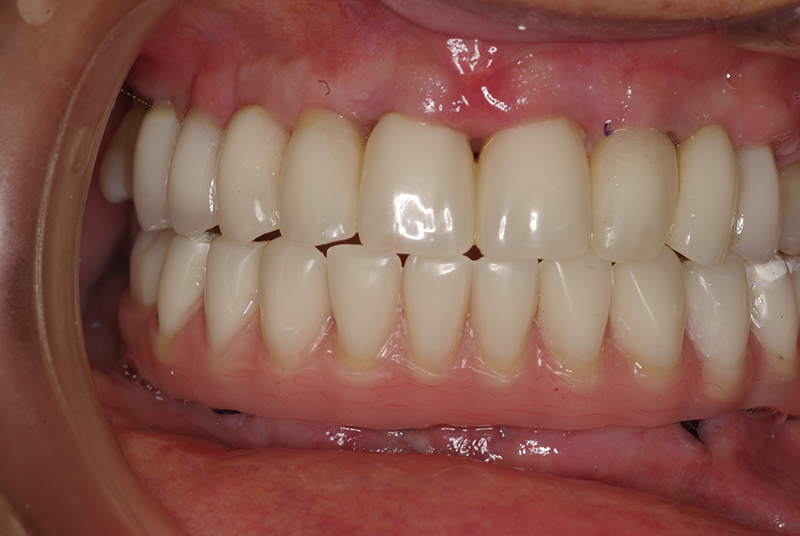

- Conforto e Estética: A prótese provisória é funcional e visualmente semelhante aos dentes naturais.

- Recuperação rápida: O paciente sai do consultório com um sorriso renovado em questão de dias.

- Melhora da autoestima: O impacto positivo de um sorriso completo é imediato, melhorando a qualidade de vida.